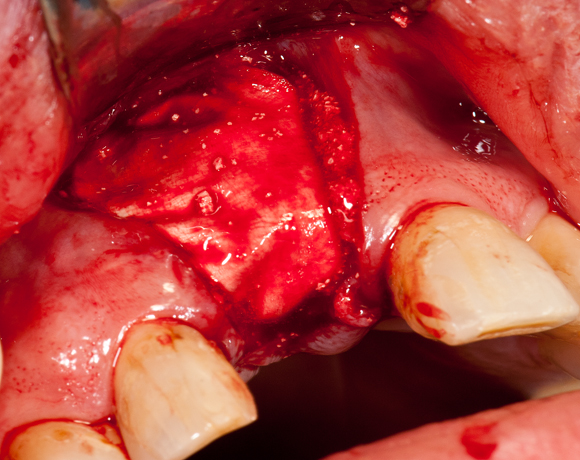

Im vorliegenden Patientenfall sollte ein Implantat für den extrahierten Zahn 11 gesetzt werden. Leider war der vestibuläre Anteil der Alveole des Zahnes 11 bei der Extraktion verloren gegangen. Damit ein ausreichendes Knochenlager zum Implantieren vorhanden ist, musste ein Knochenaufbau gemacht werden.

Bild 04: Eröffnung des OP- Gebietes durch einen Schleimhautlappen